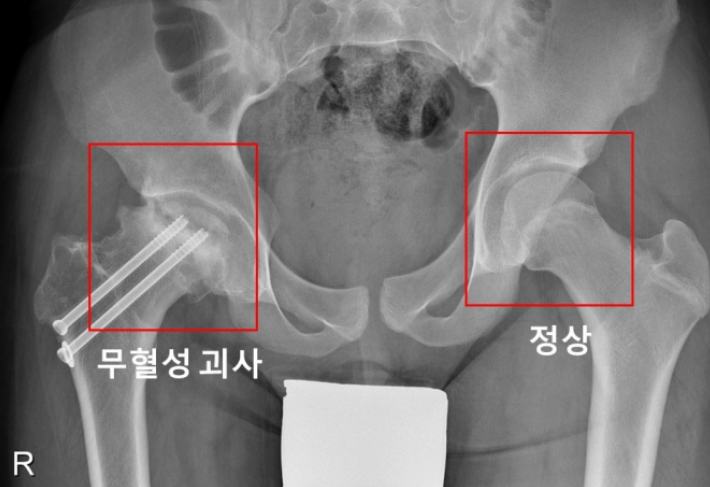

대퇴골두 골단 분리증은 대퇴골 위쪽 성장판 부위에서 대퇴골두와 그 아래의 뼈가 특별한 외상 없이 분리되는 병이라고 합니다. 진단이 지연될 경우, 대퇴비구 충돌증후군 혹은 대퇴골두가 썩는 대퇴골두 무혈성 괴사가 발생할 수 있다고 합니다.